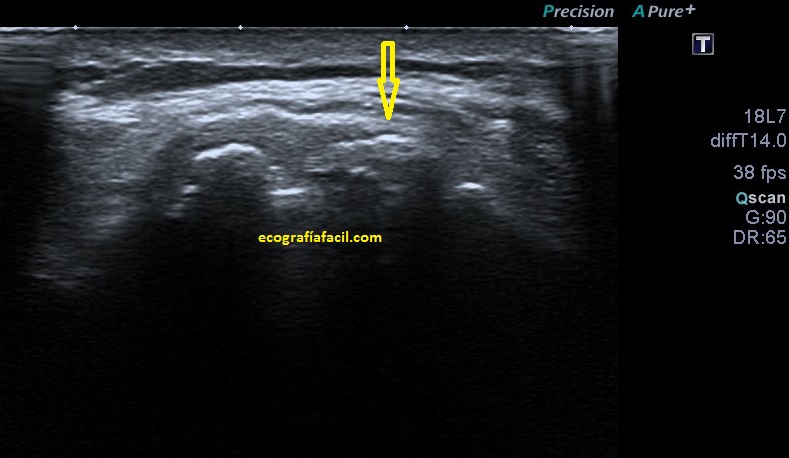

Si tu lo quieres estudiar en un corte transverso o eje corto del tendón verás como muestra de normalidad la imagen número 1. Semiológicamente es muy agradecido. Ves el tendón ovalado, hiperecogénico reposado en la corredera bicipital. El ligamento transverso humeral, hiperecogénico y lineal, anterior a la estructura tendinosa que descansa en la corredera.

Te lo digo siempre, mucho ojo con las estructuras tendinosas y la anisotropía, sobre todo la de este tendón que pese a estar luxado tiene su ecoarquitectura conservada, pero, en la imagen número 4 puedes ver la imagen del tendón con anisotropía en eje corto y te la pongo para que compares imagen 1 y 2 e imagen 4 y te des cuenta de cómo puede variar una estructura si no realizamos la técnica correctamente. Ojo con esto ya que podemos confundir a la radióloga a la hora de hacer el informe. Combatir la anisotropía es tarea exclusiva del operador

Te marco en la imagen 4 con una línea fina amarilla la corredera bicipital por si te había costado ver la relación con el tendón desplazado y que está indicado con la flecha amarilla, pero anisotrópico.